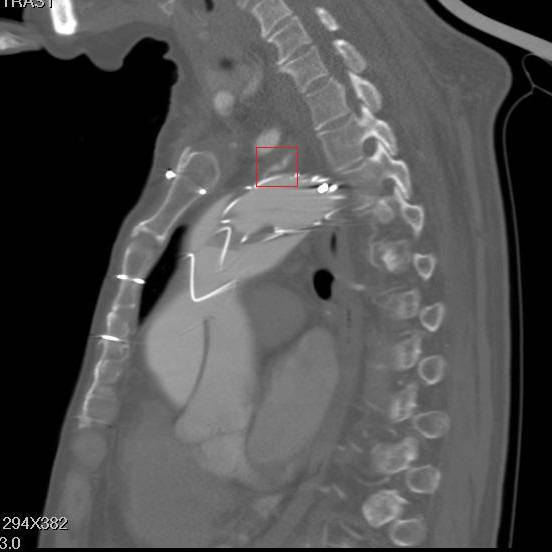

矢状面重建,胸骨钢丝很明显,方框示左颈总动脉,支架前端在假腔,后端在真腔。圆框示闭塞的人工血管

方框示左左锁骨下动脉,重度狭窄